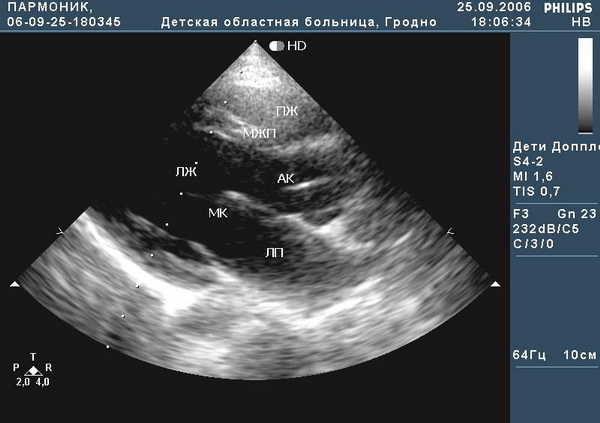

Рис.1. Положение больного с хронической сердечной недостаточностью.